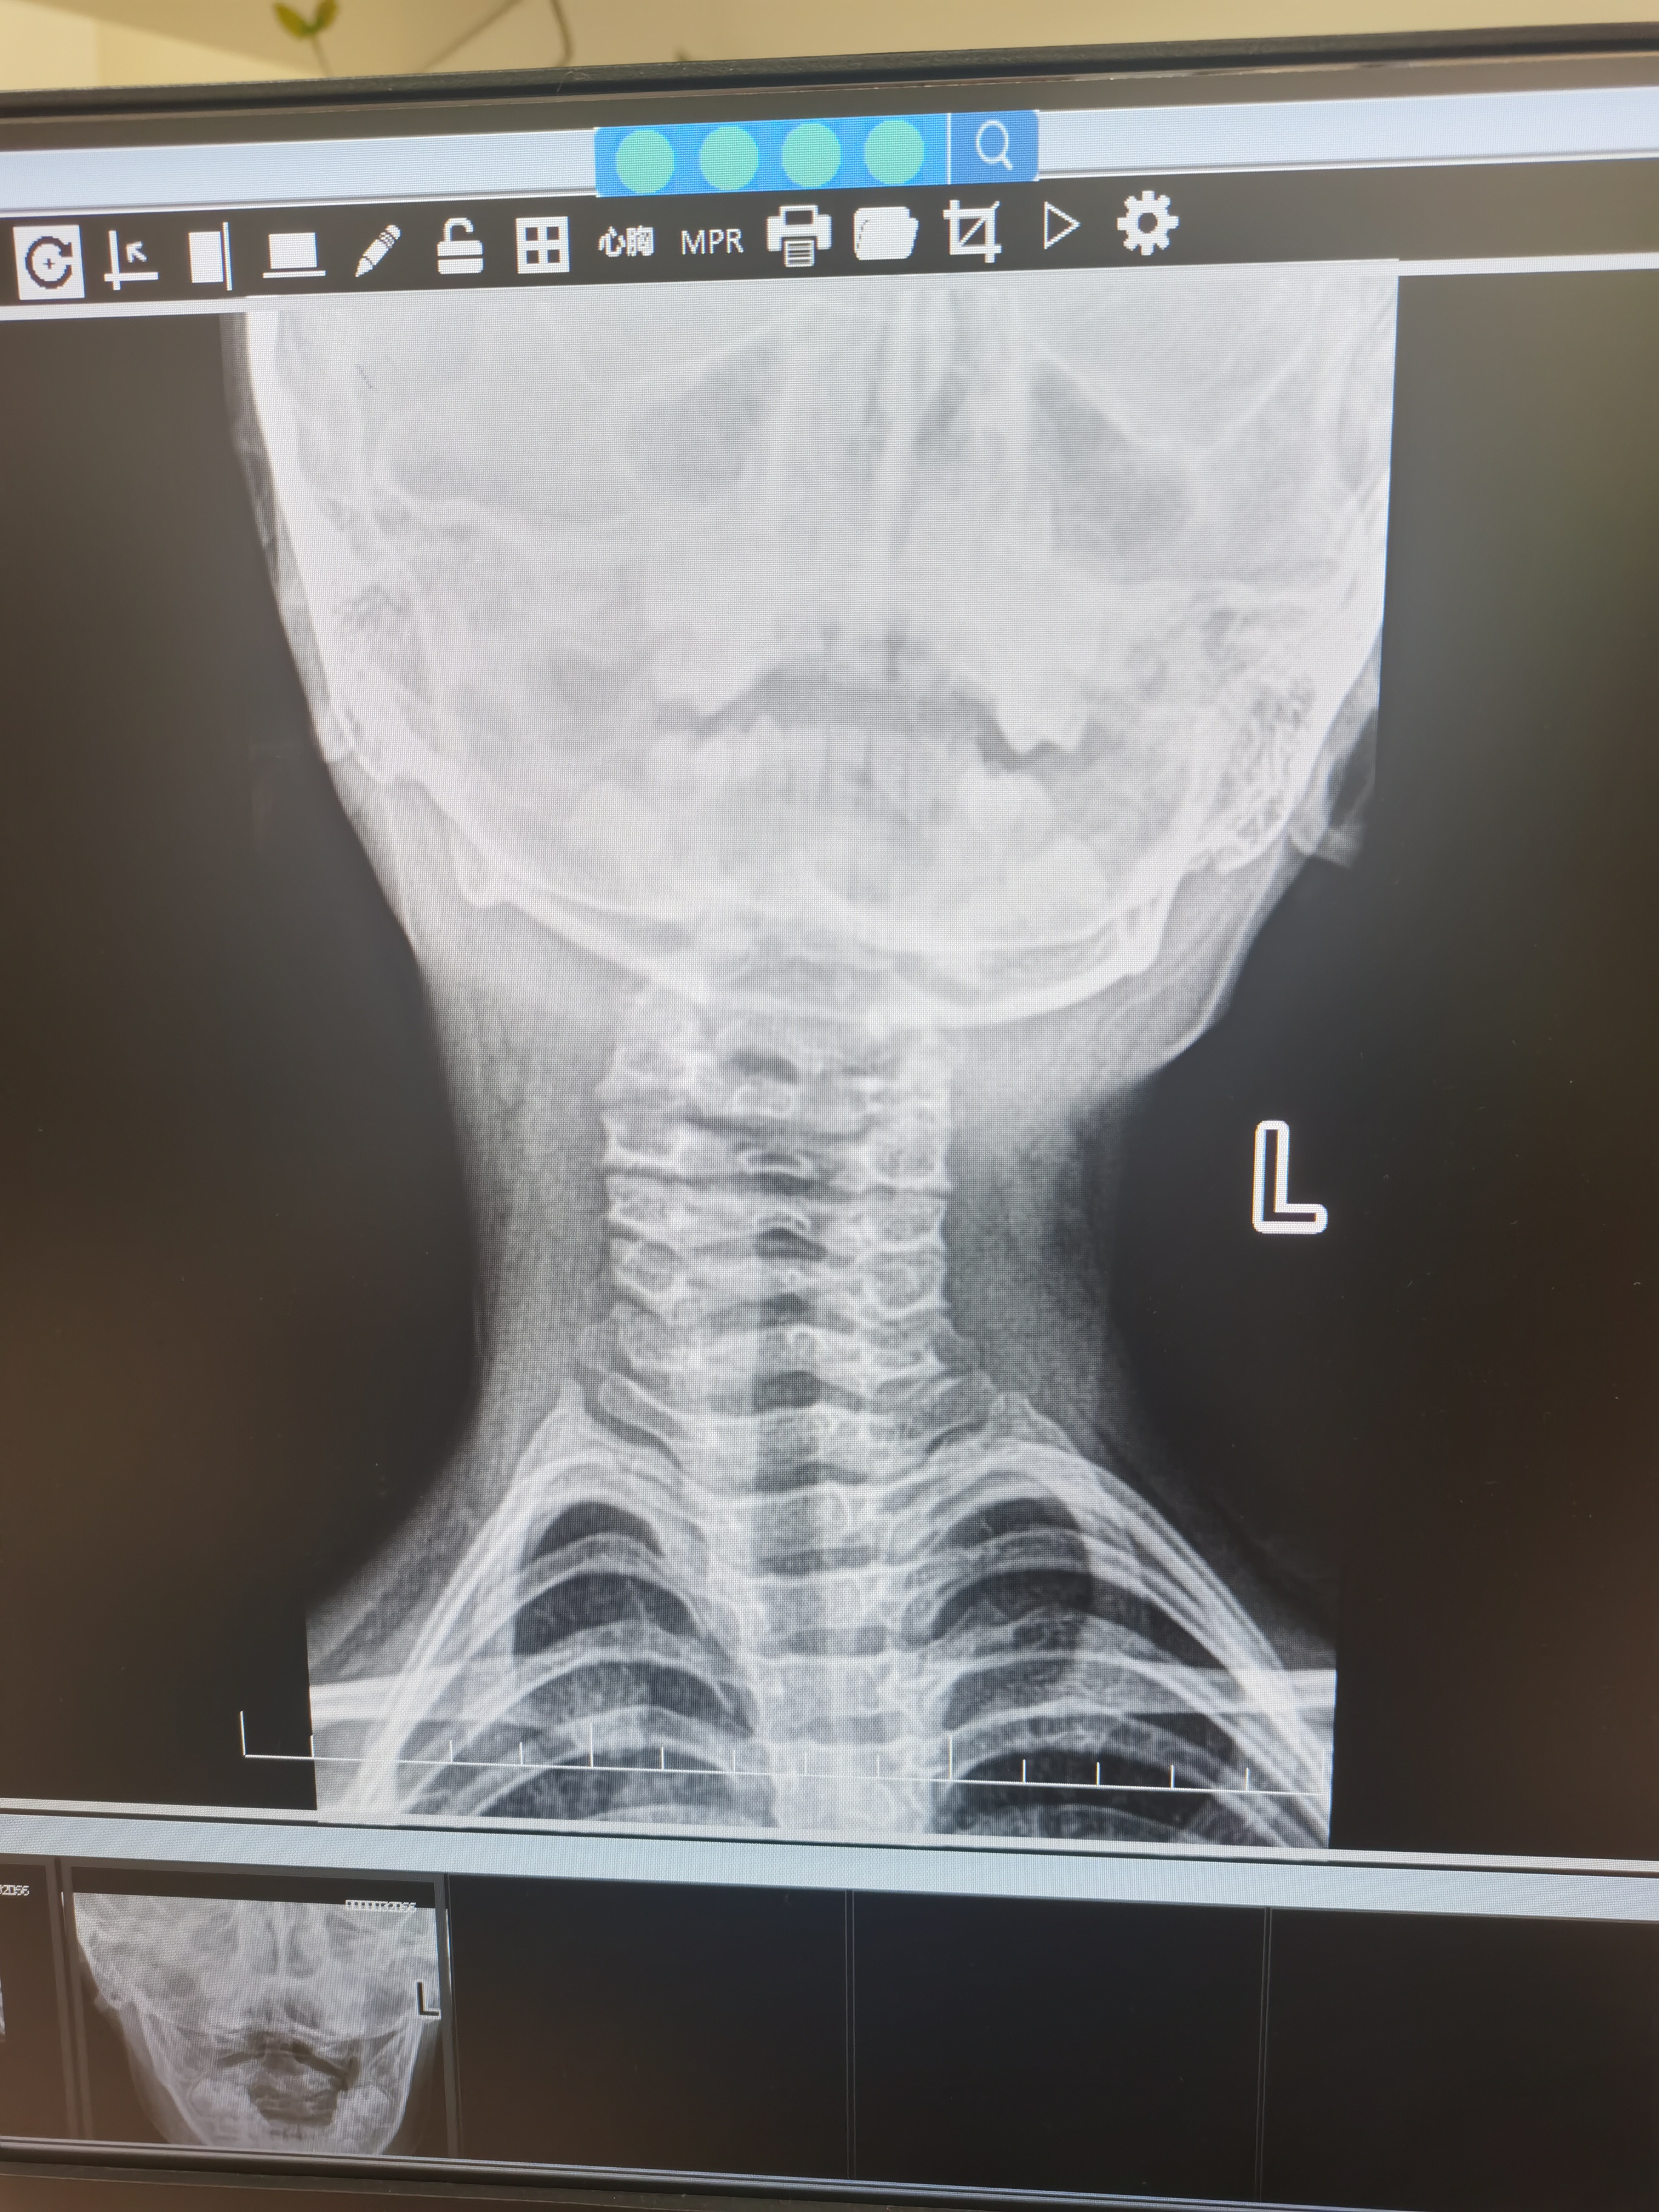

这位小男孩4岁了,清早起床后出现头位向左侧旋转固定,家长感觉他落枕了,特来就诊。体查发现他的颈部肌肉广泛性的紧张,头向右侧旋转不能,触诊第一节颈椎(寰椎)有左后旋转,行颈椎X片:颈椎整体都有左后旋转,看片子各个颈椎后面的尾巴(棘突)就像一列旋转楼梯一样,(见下图)

并且生理曲度都变直了,(见下图)